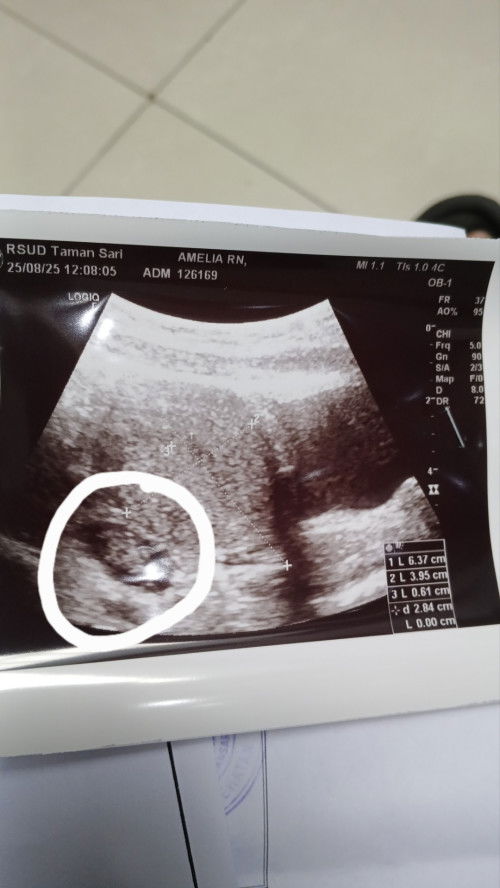

Di tespack garis 1 tebel, tapi di usg udah seperti ini, ini perkiraan udah hamil belom yaa.

Haid tanggal 15 juli, agustus ini belom haid juga.